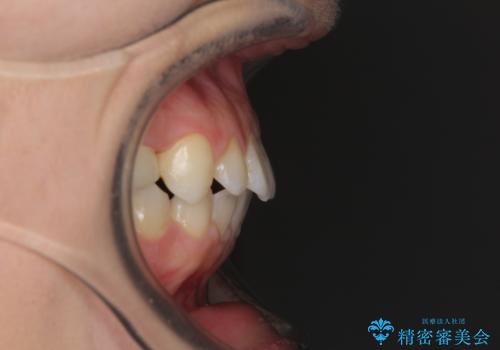

- 歯の欠損による隙間だらけの歯並びを気にして来院された患者様です。

上顎左右1本ずつ欠損していたため、歯列矯正により欠損部位にスペースを集め、その後欠損部位をインプラントにて補綴することとしました。